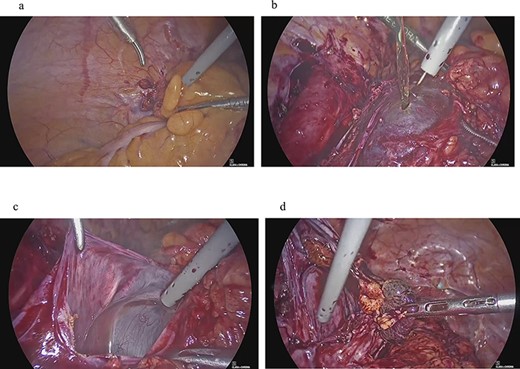

A 43-year-old woman, gravida 2, para 2 was diagnosed with uterine myoma and underwent TLH. No abnormal intra-abdominal findings, such as adhesions, endometriosis or ovarian cysts, were detected. As shown in Fig. 2a, no abnormal findings, such as adhesions, were detected at the end of surgery or 2 months later.

Clinical findings of case 2 (before surgery for PIC). (a) Findings at the end of TLH. No abnormal findings were detected. (b) An US image of PIC. The major axis was 95 mm. An ovary with a normal appearance was observed within the multilocular cyst.

Four years and 6 months after surgery, she presented with lower left abdominal pain. A multilocular cyst, measuring ~10 cm, was detected on the vaginal stump by transvaginal US (Fig. 2b). Since the cyst was considered to be causing her symptoms, emergency surgery was performed. Adhesions were observed in the left adnexal region, and a clear yellow liquid was retained in the cavity formed by the adhesions (Fig. 3). The adhesions were removed by laparoscopic surgery and left adnexal excision was performed, which ameliorated her symptoms.